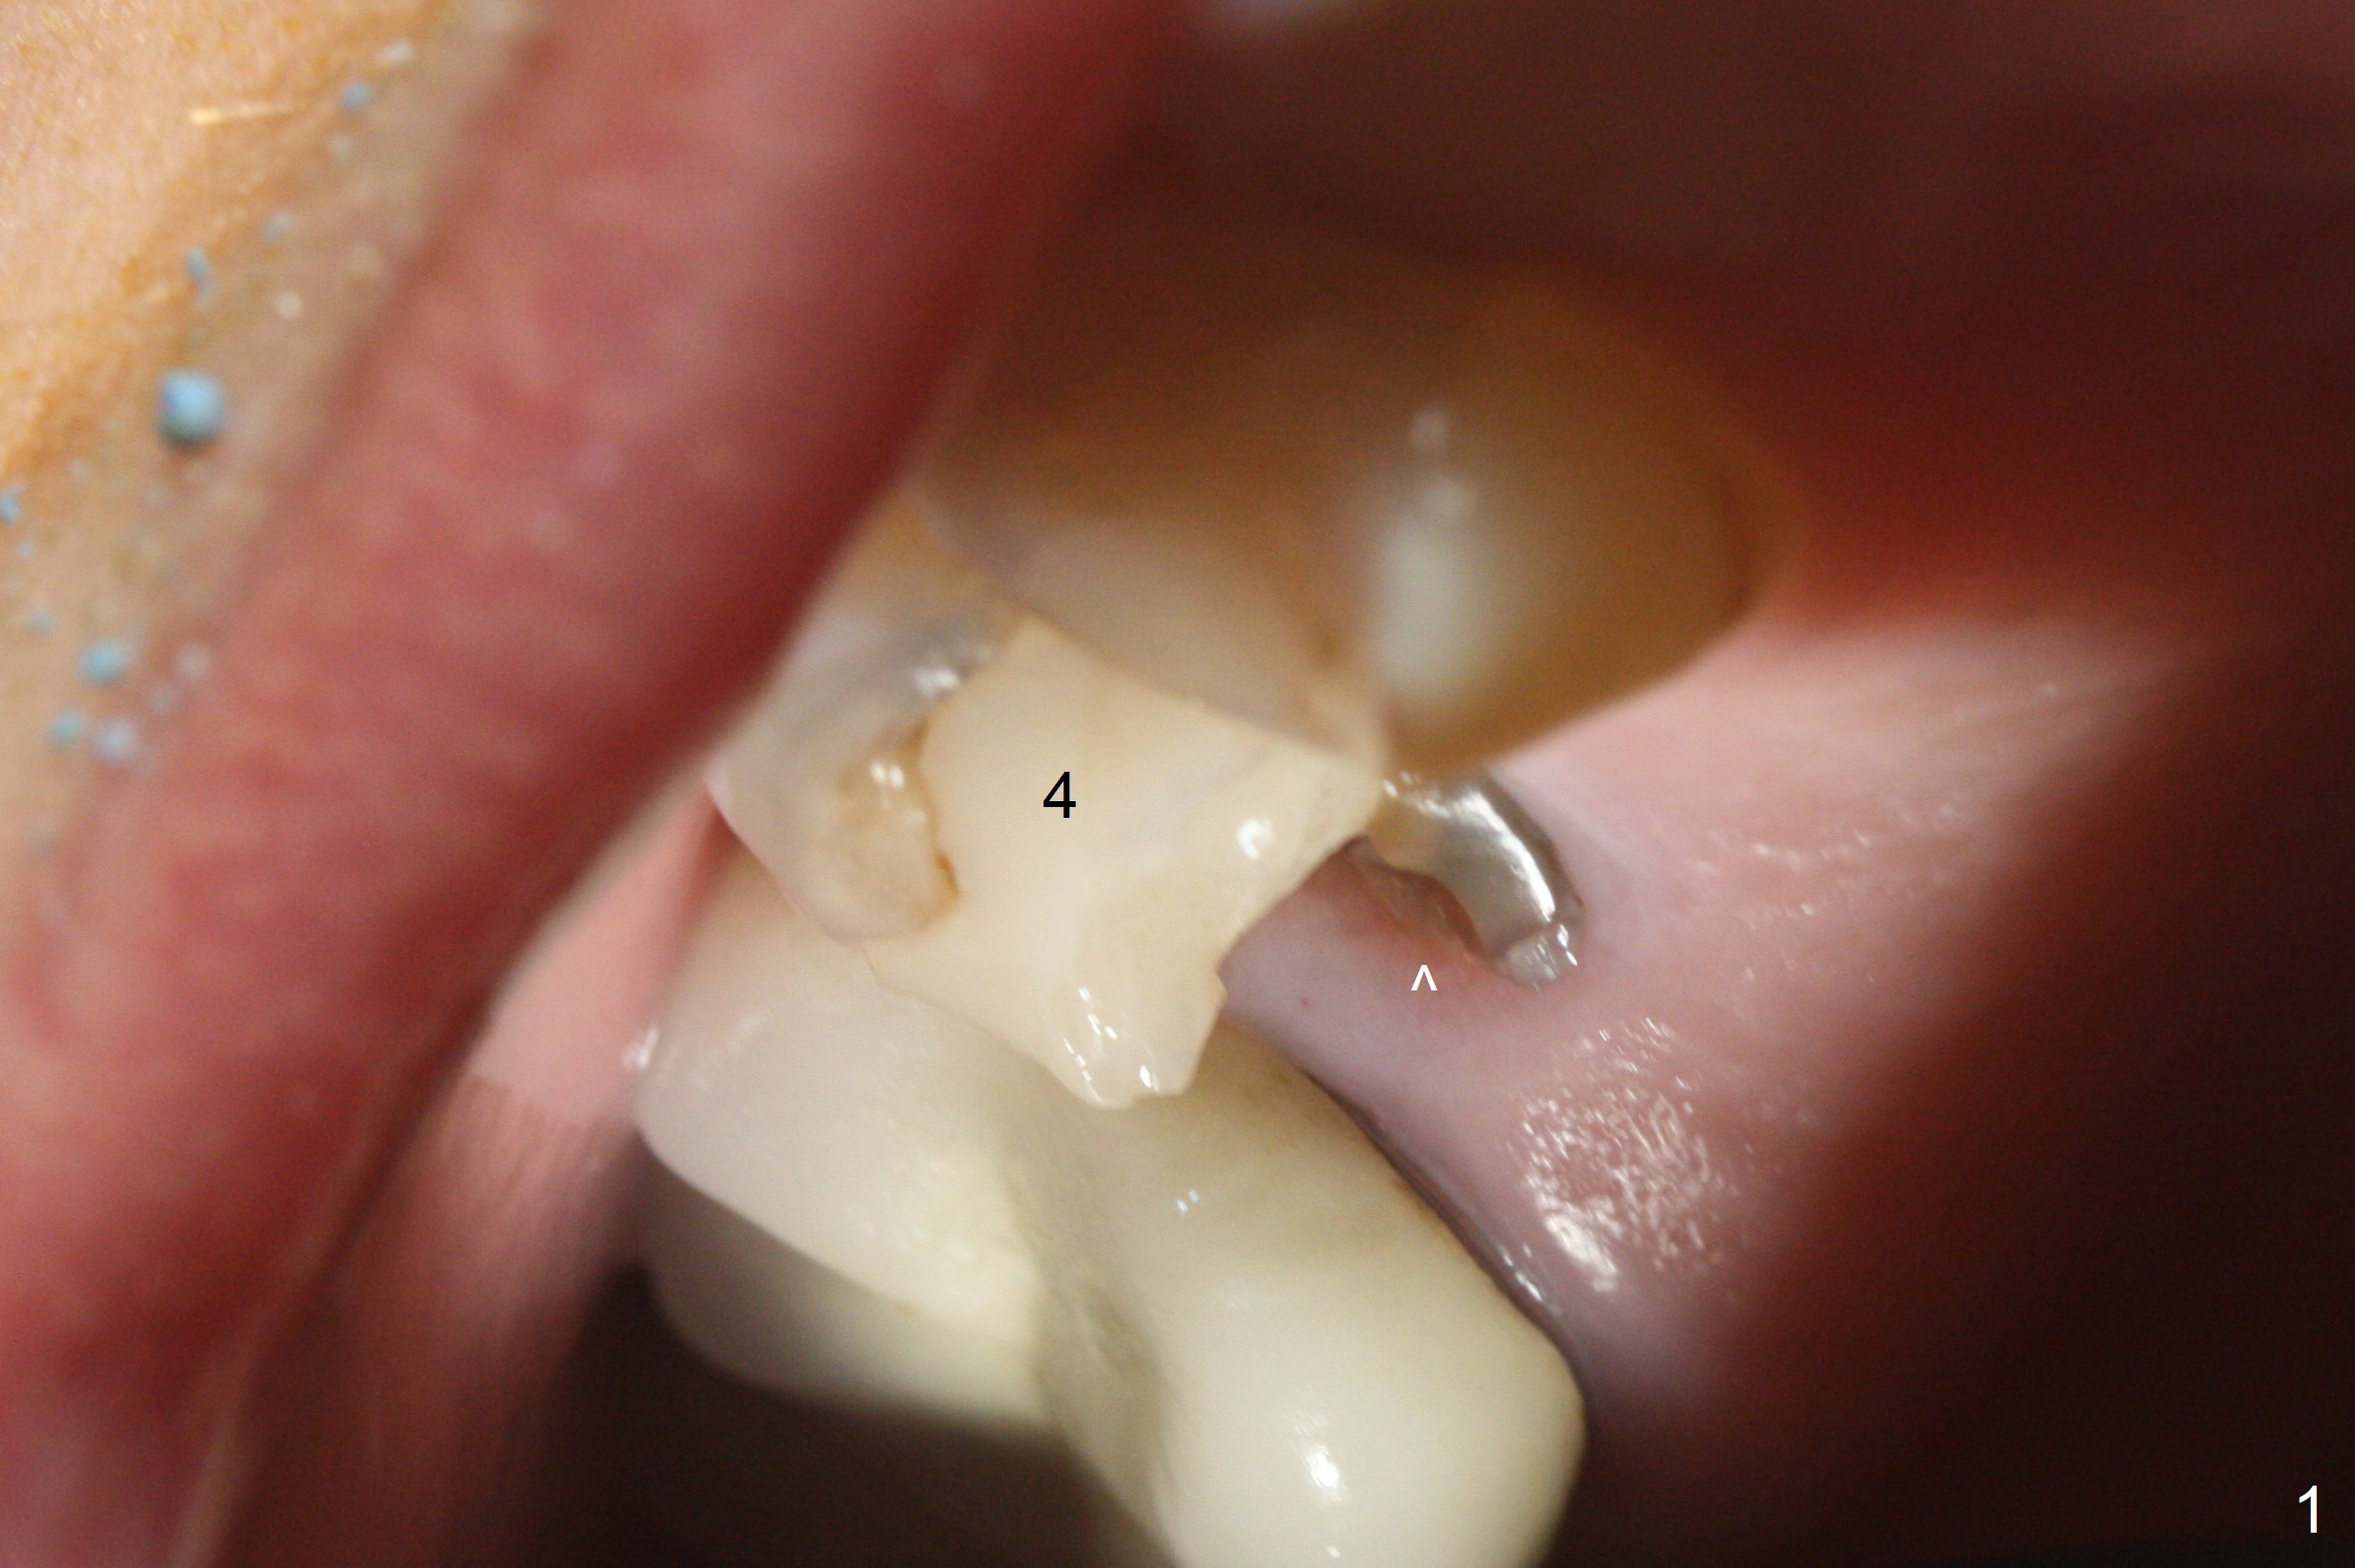

After extraction of the tooth #4 with palatally subgingival fracture (Fig.1 ^), white hard tissue is found in the socket, the density of which is hard (Fig.2 D). When osteotomy passes this portion of the bone (Fig.3 red dashed line), bone density feels reduced suddenly. The osteotomy is moved mesially slightly (Fig.4 (2.7 mm drill)). When a 3.8x15 mm dummy implant is placed with stability, there is an apical space (Fig.5 red dashed line). Therefore the final implant is longer (3.8x18 mm, <30 Ncm, Fig.6, 7). Vanilla graft is placed around the implant and a 4.5x4(4) mm abutment is placed immediately for an immediate provisional (Fig.8). Although the provisional easily dislodges in spite of remake, the implant seems osteointegrated with decreased space 4 months postop (Fig.9). The gingiva is healthy, although it covers the abutment margin partially. Gingivectomy appears necessary for impression.